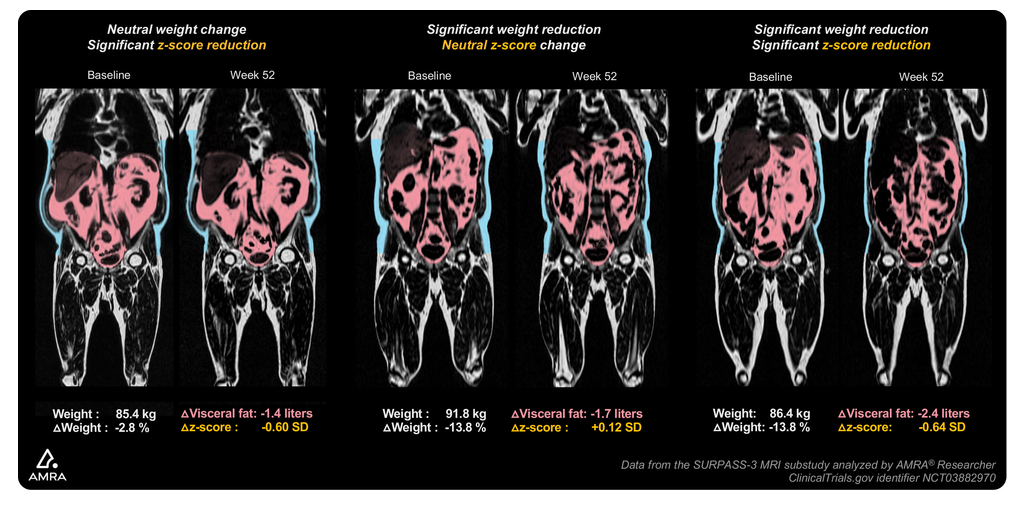

AMRA Medical’s Innovative Fat Z-Score Biomarkers Show Tirzepatide Treatment is Associated with a Potential Targeted Effect on Visceral Fat and Liver Fat

Exploratory analysis from the SURPASS-3 MRI study shows significant reduction of both visceral- and liver fat z-scores, and a shift towards a more balanced fat distribution... Read more.